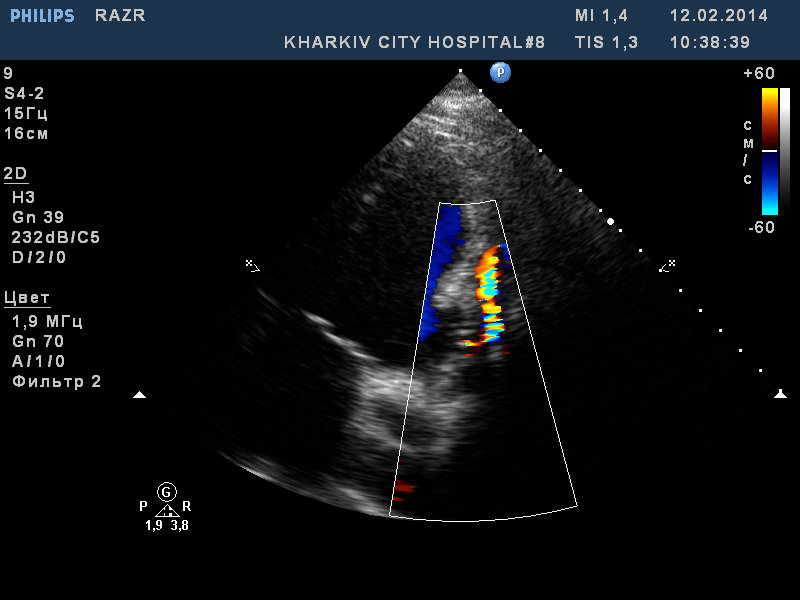

У данного пациента состояние после пластики разрыва МЖП (несколько лет назад на фоне инфаркта), решунт до 3.0мм по ширине потока, дилатация левых полостей, акинезия базальных нижнего, нижне-перегородочного,заднего сегментов левого желудочка, гипертрофия левого желудочка.